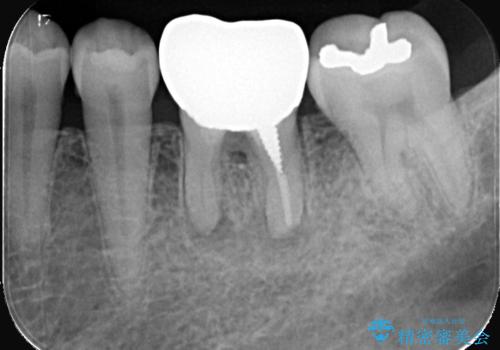

根尖性歯周炎|分岐部病変|パーフォレーション|インプラントで治療

- レントゲン検査にて、根尖および側枝付近に骨の透過像が認められました。

さらに精査したところ、根のパーフォレーション(根に穴が開いてしまっている状態)が確認されたため、

患者様と相談のうえ、インプラントによる治療をご希望され治療を行いました。